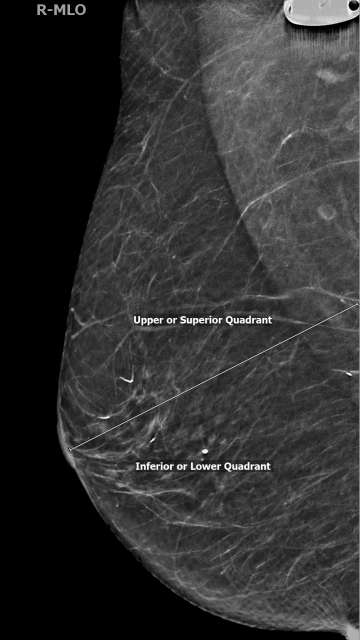

In the MLO view, lesions above the nipple are in the superior/upper quadrant while lesions below the nipple are in the inferior/lower quadrant. The superior quadrant spans from 9:00 and 3:00, while lower quadrant spans from 3:00 to 9:00 in a clockwise orientation (Figure 2). In the CC view, lesions lateral to the nipple are in the lateral/outer quadrants while lesions medial to the nipple are in the medial/inner quadrants. The lateral quadrants in the left breast span from 12:00 to 6:00, however the lateral quadrants of the right breast span from 6:00 to 12:00 (both in a clockwise orientation). Similarly, medial quadrants in the left breast span from 6:00 to 12:00, while in the right breast the medial quadrants span from 12:00 to 6:00 (Figure 3).